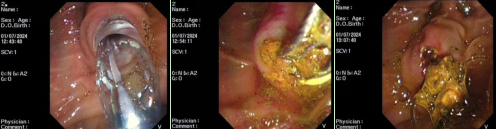

病例1

患者,男,85岁,主因“发现胆总管结石伴胆管炎,胆囊内胆汁淤积2个月”入院,曾就诊我院介入治疗科行PTCD及胆囊造瘘治疗,既往心肌梗死行冠脉支架置入、肺结核病史、肺大疱手术史,患者再次入院行内镜下逆行胰胆管造影术并胆总管取石治疗。